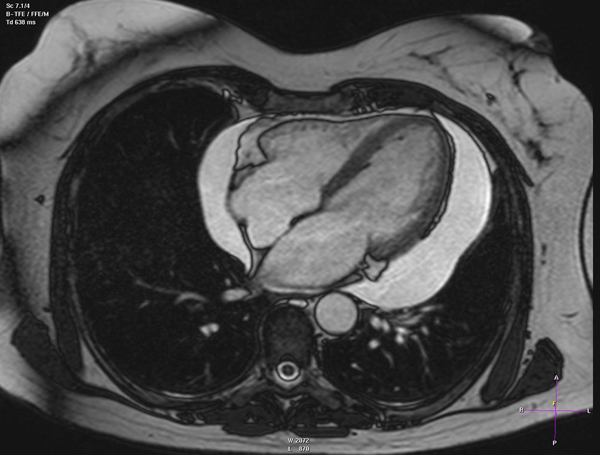

Heart Failure

Valvular Heart Disease